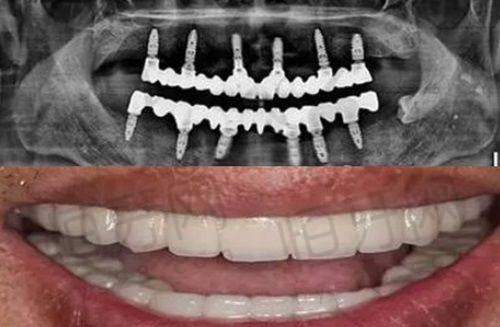

种植牙:医院引进了精良的数字化口腔诊疗设备,如CBCT、3D导板种植等,为种植牙手术提供了精细的诊断和规划。在种植牙过程中,医生可以根据患者的口腔情况和需求,选择合适的种植体品牌和型号,实现个性化的种植修复。同时,医院可能开展微创种植技术,减少手术创伤,缩短患者的修复时间。

技术设备优势:医院引进了数字化口腔诊疗设备,如CBCT、3D导板种植等。CBCT能够提供口腔内部的三维图像,帮助医生更正确地了解患者的口腔结构和病变情况,为诊断和治疗提供有力的支持。3D导板种植技术则可以在手术前严谨规划种植体的位置和方向,提高种植手术的成功几率和精细度。此外,精良的设备还能减少患者的就诊时间和痛苦,提升诊疗体验。

CBCT:这是一种精良的口腔三维成像设备,它能够提供口腔内部的详细三维图像,包括牙齿、牙槽骨、神经等结构。与传统的二维X光片相比,CBCT具有更高的分辨率和更正确的诊断信息。在种植牙手术前,医生可以通过CBCT了解患者的牙槽骨密度、高度和宽度,严谨规划种植体的位置和方向,提高种植手术的成功几率。在正畸治疗中,CBCT可以帮助医生更好地了解患者的牙齿和颌骨的关系,制定更合理的正畸方案。

3D导板种植设备:3D导板种植技术是一种基于数字化技术的种植方法。在手术前,医生会根据患者的口腔CBCT数据和口腔模型,设计出个性化的种植导板。种植导板可以严谨引导种植体的植入位置和方向,减少手术误差,提高种植的精细度。同时,3D导板种植技术还可以减少手术创伤,缩短手术时间,降低患者的痛苦和修复时间。

患者A:“我在南昌达芬奇口腔医院(进贤总院)做了种植牙手术,整个过程非常顺利。医生的技术特别不错,术前通过CBCT和3D导板种植技术为我制定了详细的手术方案,手术过程中几乎没有感觉到疼痛。术后修复也特别快,现在我的牙齿就像自己的真牙一样,非常感谢医院的医生和护士。”